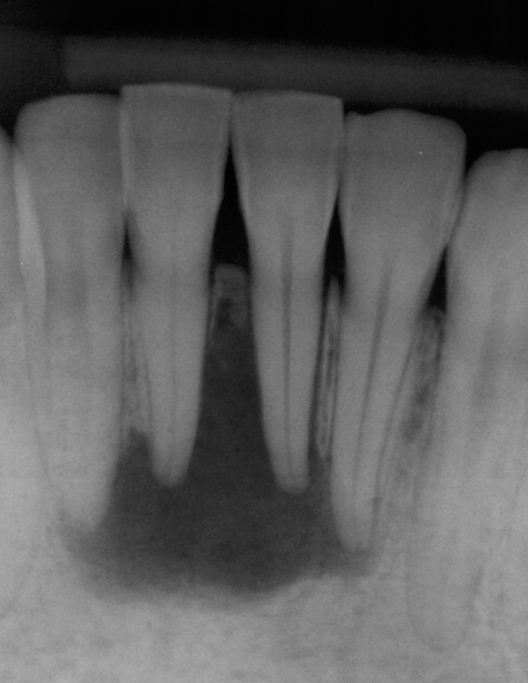

Long Term CaOH Cases

12 Month CaOH Treatment

14 Months CaOH Treatment